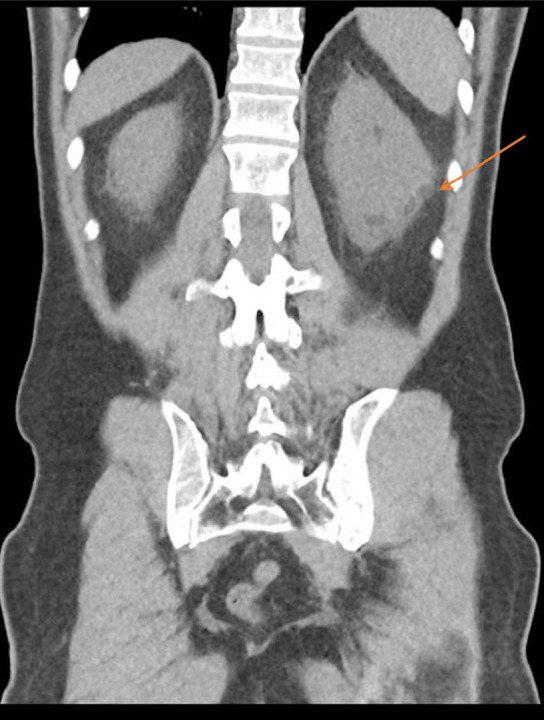

一位患有膀胱癌的62岁男性患者被转介到我们的机构进行锝-99m亚甲基二膦酸盐骨显像以评估骨转移。虽然骨扫描未显示异常摄取,但全身扫描在左侧肾周和骨盆区域检测到骨外摄取。计算机断层扫描显示穹窿破裂,示踪剂在肾周聚集。我们的诊断非常一致,并以经皮引流术治疗肾周尿漏的治疗态度为导向。

A 62-year-old male patient, with bladder carcinoma, was referred to our institution for Technetium-99m methylene diphosphonate bone scintigraphy to assess for bone metastasis. While the bone scan showed no abnormal uptake, extraosseous uptake was detected in the left perirenal and pelvic regions on the whole body scan. Computed tomography showed fornix rupture and demonstrated tracer pooling in the perirenal collection. Our diagnosis was very consistent, and oriented the therapeutic attitude towards a percutaneous drainage for the perinephric urinary leak.